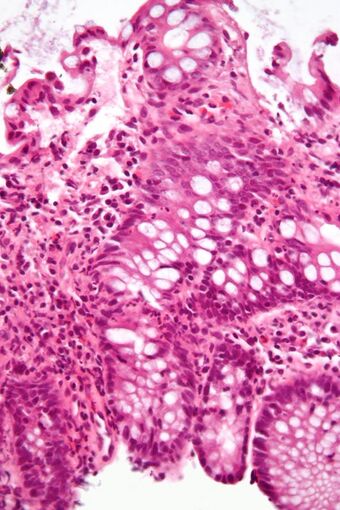

| Micrograph showing inflammation of the large bowel in a case of inflammatory bowel disease. Colonic biopsy. H&E stain. |